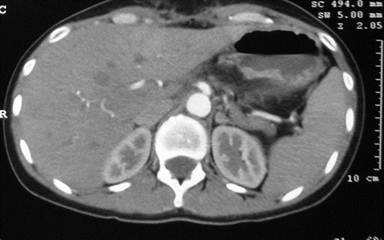

The nasogastric tube was removed on the third postoperative day. Oral intake started 5 days after surgery. The hospital stay was 12 days. Pathologic findings showed a well-differentiated neuroendocrine tumor. No postoperative diabetes mellitus or exocrine insufficiency was noticed. The patient continues to be well after a 10-month follow-up without pancreatic insufficiency or local recurrence, and CT has demonstrated real splenic perfusion by the collateral vessels on CT (Figures 5 and 6).

Figure 5. Perfusion of the remnant splenic artery by collateral vessels on contrast- enhanced CT. |